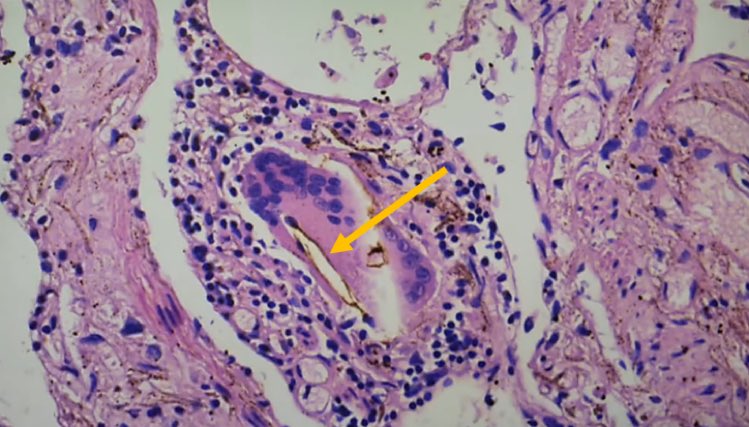

التهاب عضلة القلب اللمفاوي ، التهاب غشاء القلب ، التهاب التامور ، "غلبة الخلايا الليمفاوية" :

⁃نموذجي للعدوى الفيروسية

⁃يصعب التعرف عليها بالميكروسكوب ،

⁃غالبًا ما يُساء تفسيرها من الناحية النسيجية على أنها معدية (الخلايا الحبيبية!). 6️⃣

⁃عادةً ما تكون البؤر صغيرة متعددة ، وبالتالي لا يتم اكتشافها في كثير من الأحيان

⁃التأثير على قدرة الضخ (تحذير: وزن القلب الحرج)